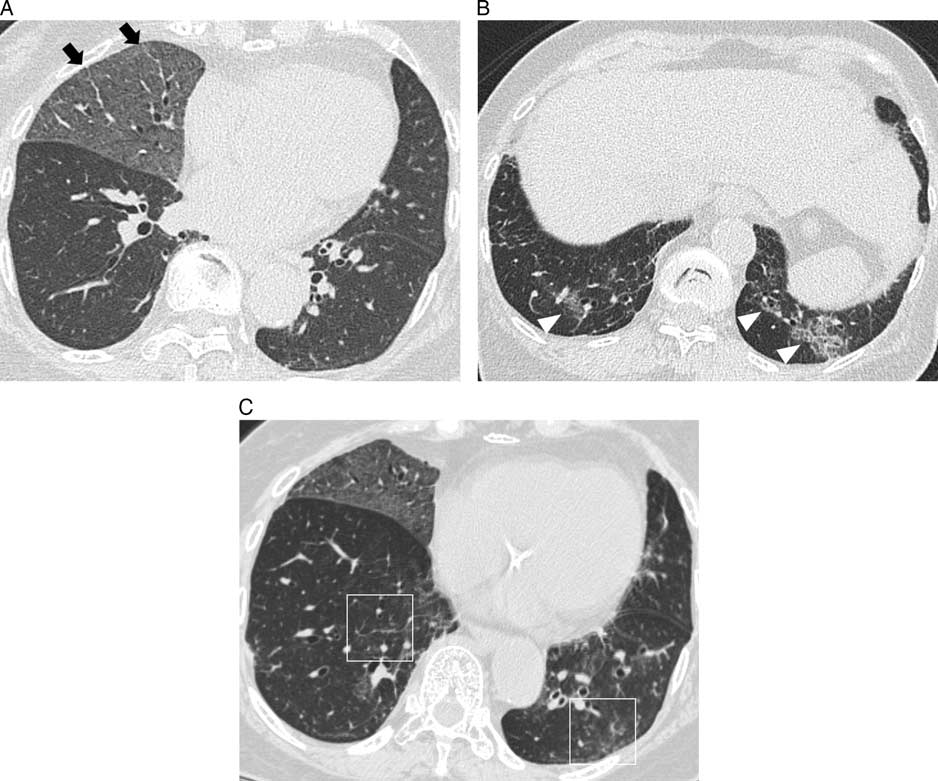

为明确诊断行支气管镜检查,支气管肺泡灌洗液呈淡黄色,分2层(图3A)。 苏丹III染色检测肺泡巨噬细胞中含有油脂成分(图3B, C),最终诊断为用芝麻油漱口引起的ELP。在指导患者戒掉此习惯3个月后,其病情及CT表现逐渐改善(图4)。

图4 停用芝麻油漱口3个月后,胸部CT示肺实质异常基本改善。